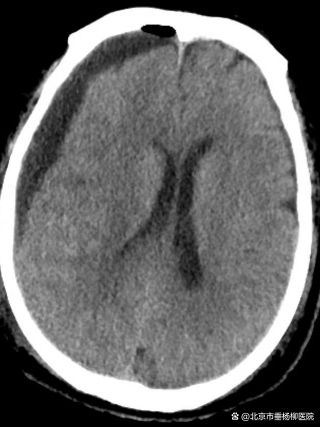

第2次术前

患者男性,69岁,因“头外伤后3周,头痛1周”就诊于北京市垂杨柳医院急诊科。头颅CT提示右侧额颞顶部慢性硬膜下血肿,量约140ml。入院后局麻下行慢性硬膜下血肿钻孔引流术,术后复查头颅CT大部分血肿排出,患者头痛明显好转,如期出院。术后1个月患者再次出现头痛,门诊复查头颅CT提示血肿复发,中线结构向左移位。再次就诊于北京市垂杨柳医院神经外科。